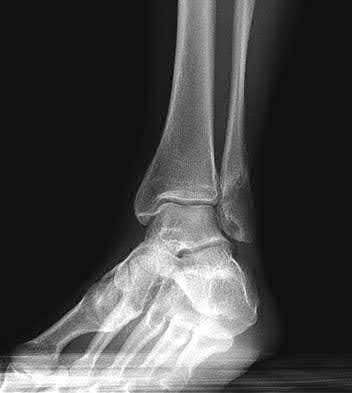

A 25-year-old female is involved in a motor vehicle collision. She presents with the isolated injury seen in Figures A through D. Her leg is swollen but her skin is intact. She has no clinical signs of compartment syndrome. Which of the following treatment options will allow for maintenance of fracture alignment and minimize the risk of soft tissue complications?

The patient presents with a closed distal third metaphyseal-diaphyseal distal tibia fracture with simple intra-articular extension. Immediate intramedullary nailing along with percutaneous fixation of the articular component provides appropriate restoration of length, rotation and alignment and minimizes the risk of wound complication.

Displaced distal third tibia fractures may be associated with simple intraarticular extension. Operative treatment of intra-articular distal tibia fractures has historically been performed with open reduction and internal fixation. Early open reduction and plate fixation of pilon fractures has been associated with high rates of infection and wound complication. In select patterns with simple articular extension, percutaneous screw fixation and medullary nailing may provide appropriate reduction with minimal soft-tissue risk.

Figures A and B demonstrate a distal third tibial shaft fracture with simple intra-articular extension. The axial and coronal CT cuts in Figures C and D further clarify the articular injury. Illustrations A and B demonstrate a comminuted distal third tibial fracture with simple intra-articular extension. Illustrations C and D are fluoroscopic images of the same injury after intramedullary nailing and percutaneous fixation of the articular component.